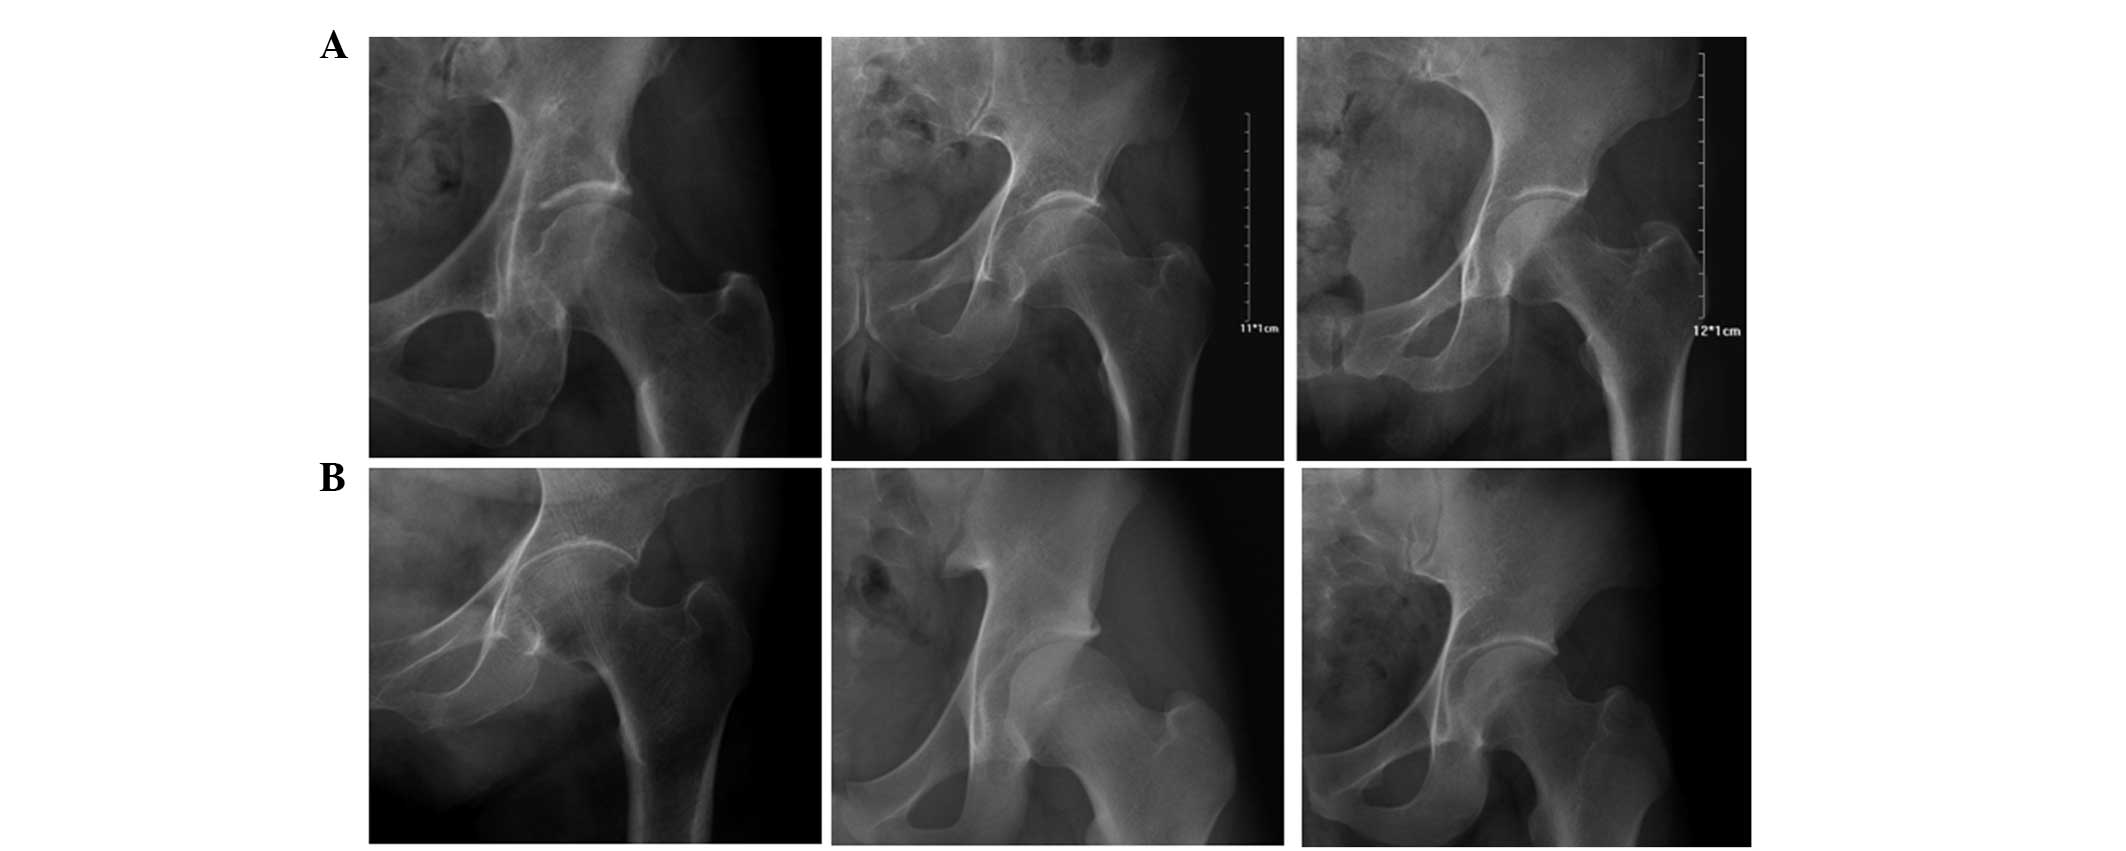

According to the clarity degree of the medial edge of the acetabular sourcil on radiograph, the hips were divided into the clear-edge (Fig. 2A) and blurred-edge (Fig. 2B) groups. The hips belonging to the blurred-edge group could not be used for Tönnis angle measurements. All measurements were performed digitally using the Huahai MedPACS picture-archiving communication system (Huahai Medical Info-Tech Co., Ltd., Xi’an, China).

Figure 2

Radiographs showing (A) acetabular sourcils with clear medial edges, which can be used to measure the Tönnis angle, and (B) hips assigned to the blurred-edge group, in which the medial edges of the acetabular sourcils are indistinct.